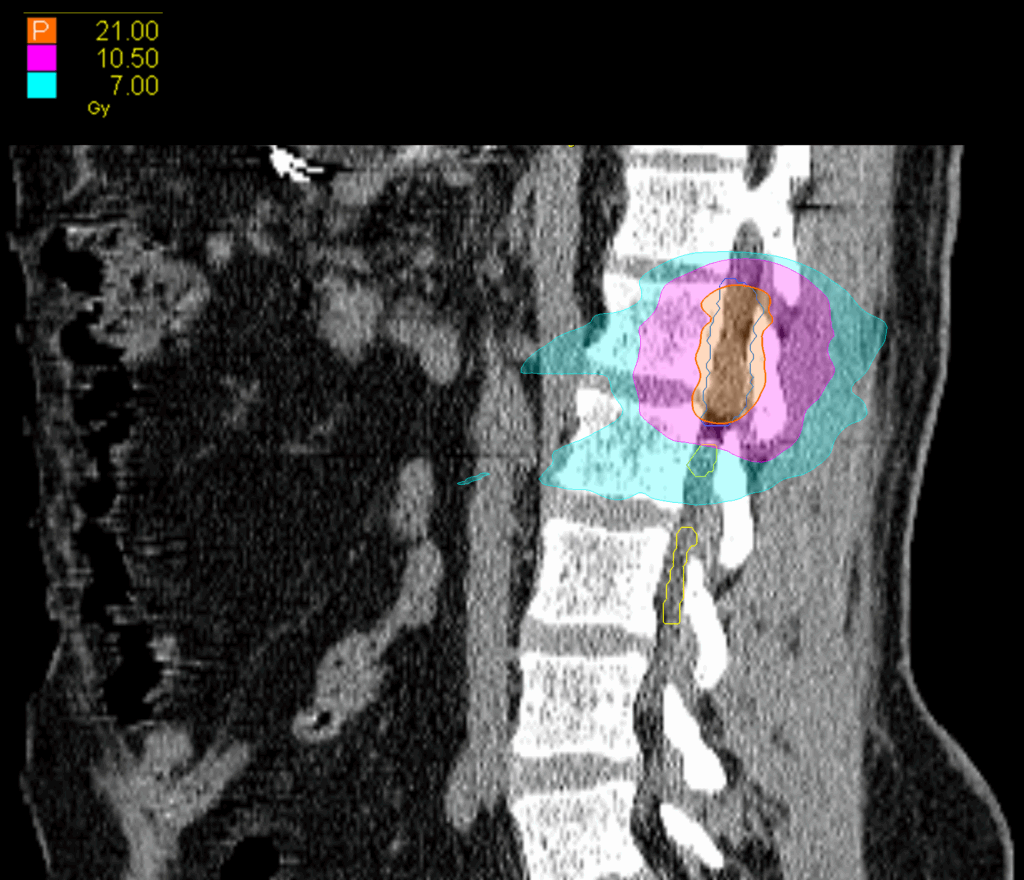

Treatment Plan Images

Fractionation

21 Gy in 3 fractions

PTV(s) Volume

PTV, 15.7 cc

Dose Distributions

- Prescription to the 77.9% isodose line

- Max. dose 29 Gy

New Conformality Index (nCI)

nCi = 1.47

Gradient Index (GI)

GI = 4.24